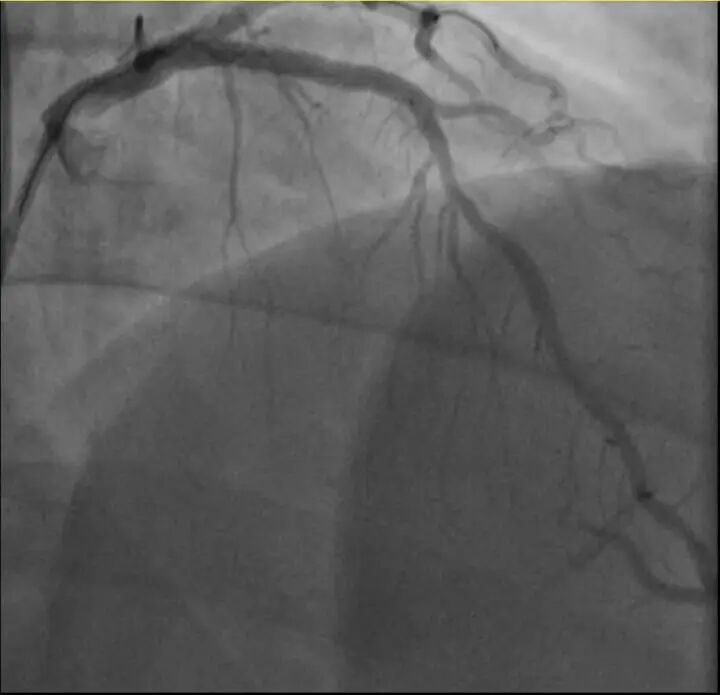

介入治疗前影像图。

浙江医院心血管内科的医生分析,剧烈运动导致这位患者心脏的不稳定斑块破裂,进而造成前降支近段次全闭塞。所幸送医及时,孙先生的身体险情被化解。

介入治疗后影像图。